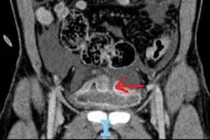

Cứu sống nam bệnh nhân 46 tuổi bị vỡ bàng quang hiếm gặp

Bệnh viện Nhân dân 115 (TP HCM) vừa tiếp nhận và phẫu thuật thành công cho một trường hợp vỡ bàng quang hiếm gặp.

Vỡ bàng quang là một cấp cứu y khoa nguy hiểm, có thể dẫn đến biến chứng nghiêm trọng như viêm phúc mạc hoặc nhiễm trùng huyết nếu không được xử lý kịp thời.